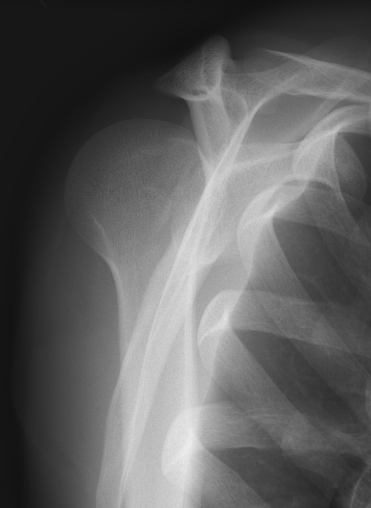

Scapular lateral

Center of the humeral head must be centered on the Y / Mercedes sign

Y is formed by

- coracoid anteriorly

- scapular spine posteriorly

- scapula body inferiorly

Normal scapular lateral

Posterior shoulder dislocation